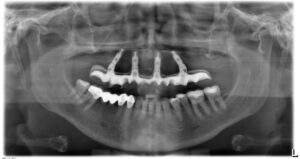

- Controllo radiografico finale: a completamento dell’intervento, eseguiamo una radiografia di controllo (OPT) per verificare l’esatto posizionamento dei quattro impianti. Spesso si noterà che i due impianti posteriori sono inclinati verso la parte posteriore dell’arcata (tilted implants), confermando il caratteristico assetto “a V rovesciata” dell’All on 4.

All on Four Senza Gengiva Finta

L’implantologia All on Four senza gengiva finta è un’opzione protesica che non prevede l’utilizzo sulle protesi dentali di gengiva artificiale. Questo approccio consente un’estetica migliore e soprattutto un aspetto più naturale delle protesi in modo da renderle perfettamente mimetizzabili.